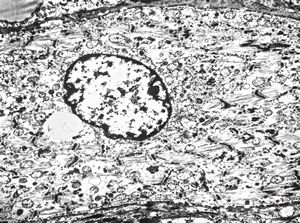

M,56y. | amyloidosis - tendon